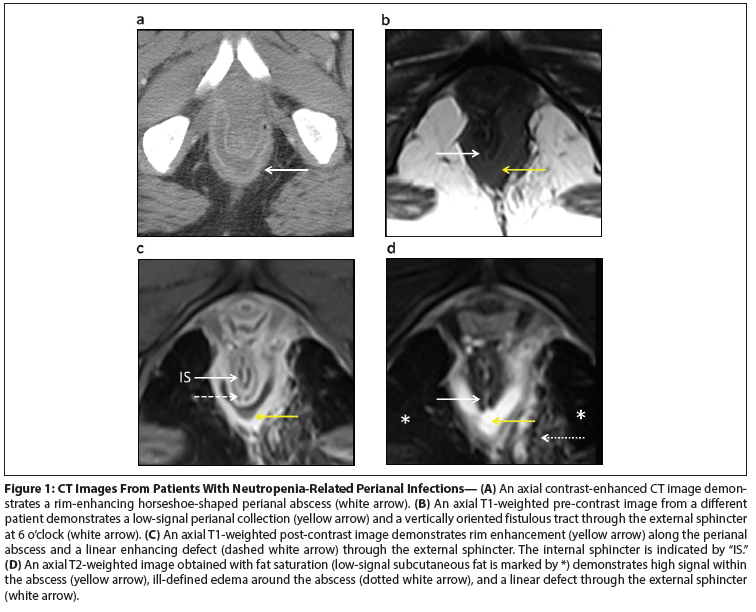

Figure 1: CT Images From Patients With Neutropenia-Related Perianal Infections

If the diagnosis is in question in a patient with perianal pain and a paucity of clinical signs, then imaging is warranted. We prefer to image with contrast-enhanced MRI. Although large perianal abscesses will be visible on a CT scan, the superior soft-tissue resolution of MRI allows for better delineation of fistulous tracts and their relationship to the internal and external anal sphincters (Figure 1A–D).[15]

On pre-contrast T1-weighted MRI images, perianal abscesses typically demonstrate low signal (Figure 1B). T1-weighted post-contrast images are helpful for demonstrating rim enhancement around fluid collections and for demonstrating enhancing walls of fistulous tracts (Figure 1C). T2-weighted images obtained with fat saturation best demonstrate fluid collections and related edema, which will appear as areas of high signal against a background of low-signal fat (Figure 1D). Finally, MRI correctly classified the location of fistulous tracts in 90% of 104 patients and can aid in operative management.[16]